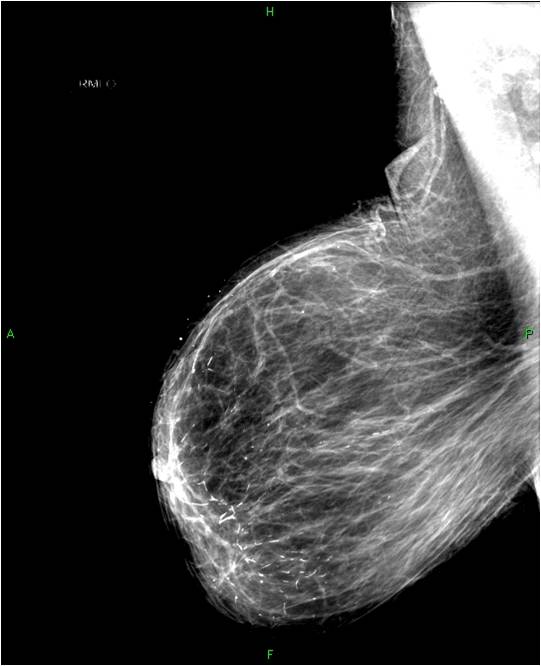

2. Digital mammography has displaced the analogue technic for today almost everywhere: (pictures 1,2,3) phosphorous plate or direct digital methods. For breast imaging the latter is the method of choice. Phases of image production separate. The image is produced on the detectors, but appears on the high resolution monitor and can be stored as a digital data set at various storage mediums (e.g.: CD, hard disk drives).

Image

Picture 2.

Picture 3.

3. Tomosynthesis: mammography images are made in 15 ° angle range ( depending on the machine 15-50°, 13-25 images). The disturbing shadows on the summation image can be eliminated by the tomograpy technic so in this way the sensitivity can be increased.

Mammography exposition: all breast images have to be acquired at least in two directions!

Standard images: cranio-caudal (CC), half-oblique, medio-lateral oblique (MLO).

Additional images: lateral (medio-lateral, latero-medial) magnified images etc.